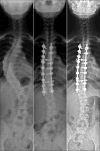

Background: Correcting the scoliosis and stabilizing the spine in the corrected position is the basis of treatment for adolescent idiopathic scoliosis (AIS). Spinal instrumentation and derotation are the principle steps of surgery for any type of AIS. A perspicuous understanding needs to be attained regarding derotation maneuvers in practice; therefore, we intend to compare radiological outcomes following concave and convex rod derotation maneuvers to analyze their efficacy to correct selective Lenke's Type-1 scoliosis.

Materials and methods: Retrospectively, 88 patients with Lenke's Type-1 scoliosis who were operated with selective thoracic instrumentation were divided into two groups depending on the derotation side. Preoperative radiographs were analyzed for curve angles, thoracic apical vertebral translation, apical vertebral rotation, and coronal/sagittal balance. Postoperative and followup assessment was focused on curve correction. Correction rate of main thoracic (MT) curve and its corresponding loss of correction at final followup are calculated.

Results: Concave group (n = 40; age 13.8 ± 1.9) and the convex group (n = 48; Age 14.3 ± 2.4) showed similar demographic characteristics. Postoperative and followup parameters showed no significant difference. Correction rate of MT curve between both groups (concave group = 69.2 ± 10.5%; convex group = 66 ± 12.8%; P = 0.20) was similar. There was minimal loss of correction at final followup among both groups (concave group = 2.2° ±5.4°; Convex group = 1.5° ± 4.8°; P = 0.52).

Conclusion: The study results showed similar sustained satisfactory correction of flexible Lenke's type 1 scoliotic curves irrespective of the derotation maneuver used. Adequate correction, thereby restoring balance was predominantly perceived among the entire sample. Hence, convex derotation can be considered equally effective as that of concave derotation for achieving adequate correction of selective Lenke's Type-1 scoliosis.